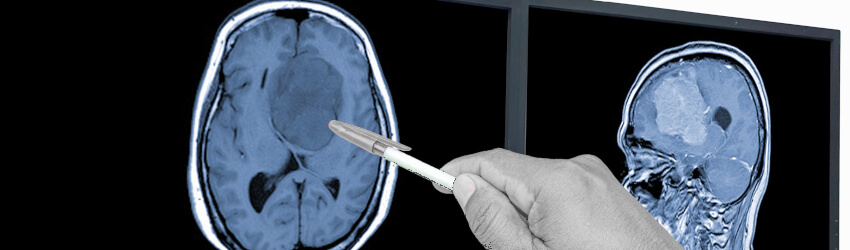

Targeting a gene-altered metabolic process in glioblastoma (GBM) could unlock new ways of treating the deadly brain cancer.

Writing in Cancer Cell, the UCLA team report that they compiled a collection of 84 GBM tumour samples, 29 orthotopic xenografts, and 43 GBM-derived cell cultures - with the aim of finding “a therapeutically exploitable link between a recurring molecular lesion and altered lipid metabolism in GBM.”